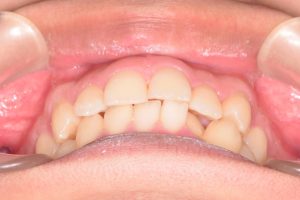

2期治療開始時(2023年7月)と装置撤去時(2025年9月)の写真です。

下から